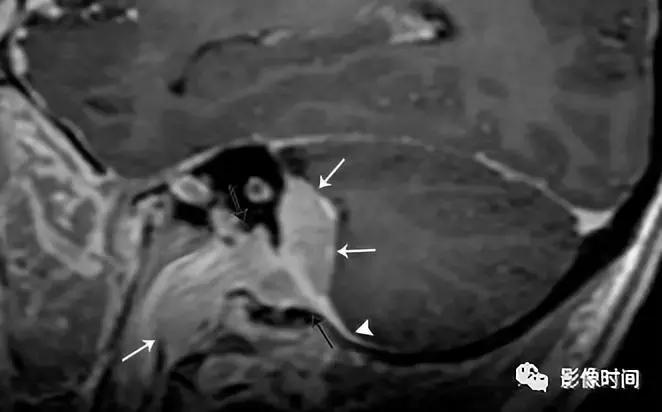

3、脑膜瘤:脑膜瘤是中枢神经系统最常见的脑外颅内肿瘤,大多数脑膜瘤发生在颅内。颈静脉孔区的脑膜瘤可向下延伸至颈动脉间隙。大多数脑膜瘤 CT 表现为等或者高密度,20% 钙化,邻近骨质表现为反应性骨质增生。在 MRI 上,脑膜瘤通常表现为 T1WI 等或稍低信号,T2WI 等或稍高信号,明显强化,可见脑膜尾征。

轴位 CT 显示病灶相邻的骨质增生(白色箭头),正常左乳突骨皮质 (黑箭头)。轴位 T2WI 病灶呈等信号 (白色箭头),向前推移颈内动脉 (i)。左侧颈内动脉的正常位置也被观察到。

矢状位 T1WI+C 病灶明显强化 (白色箭头) 从后窝延通过颈静脉孔 (黑色箭头) 延伸至右颈动脉间隙,见硬膜尾征(无尾箭头)。